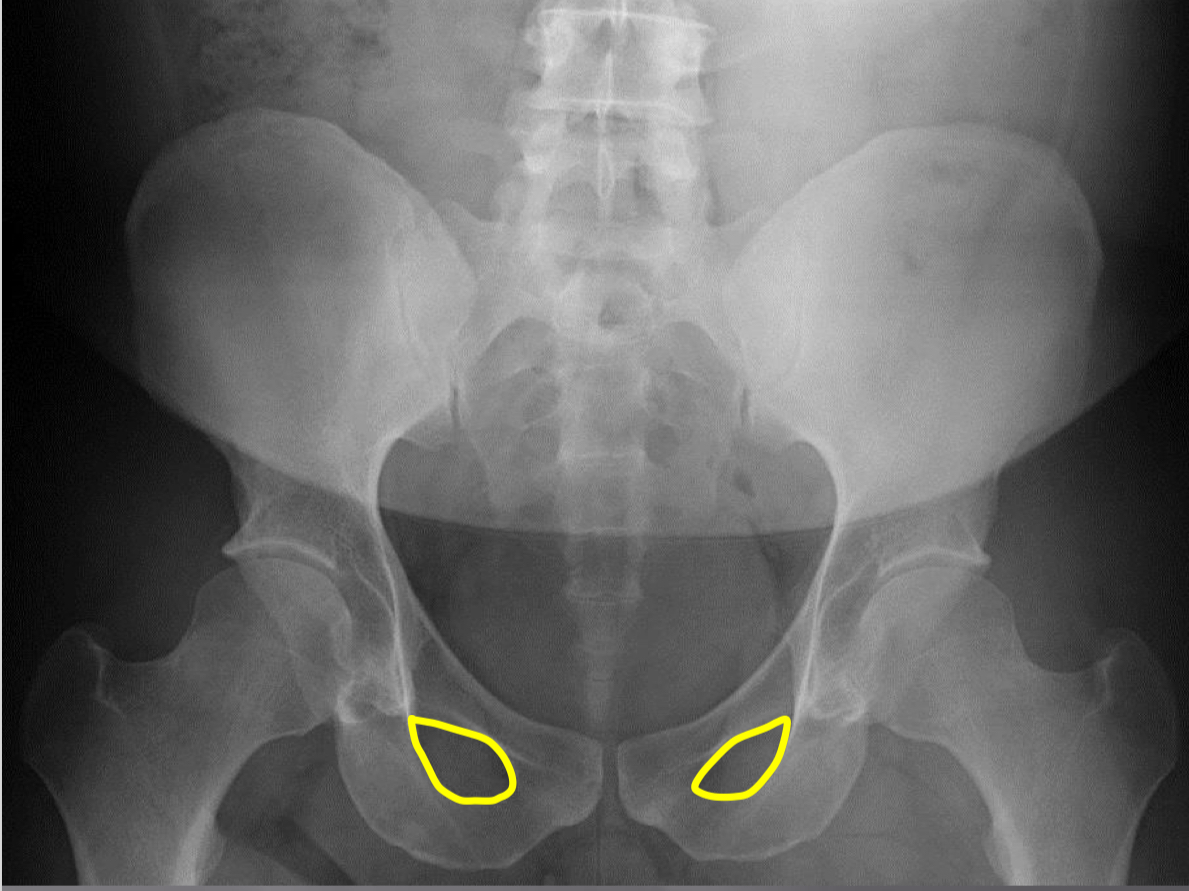

What view is this?

AP (Anterior to Posterior) LumboPelvic

What is this?

Femur Heads

What is this?

Superior Iliac Crests

What is this?

Lateral Iliac Crests

What is this?

Ischial Tuberosites

What is this?

Obturator Foramen

What is this?

S2 Tubercle

What is this?

Pubic Symphysis

What is this?

Sacral Groove

What is this?

Lateral aspect of sacrum

What is this?

Medial Aspect of Ilium